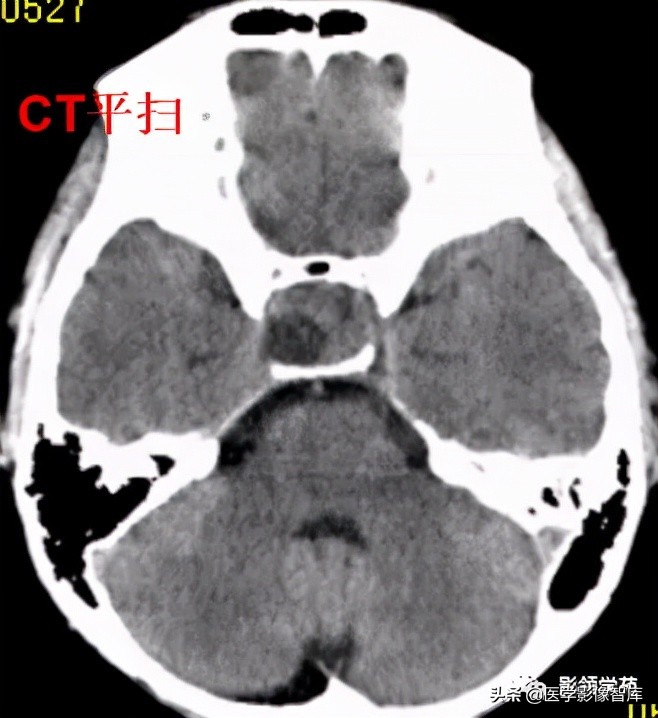

男,2岁,双视力障碍

鞍区见一类圆形囊性肿块,呈长T1长T2信号,囊壁厚薄不均。

囊壁呈环状强化,囊内未见明显强化。病灶占据蝶鞍、鞍上池及第三脑室前部,边缘清楚。

鞍区见一类圆形囊性肿块,囊壁呈蛋壳样钙化。肿块向下压入蝶鞍,向上达到第三脑室水平。